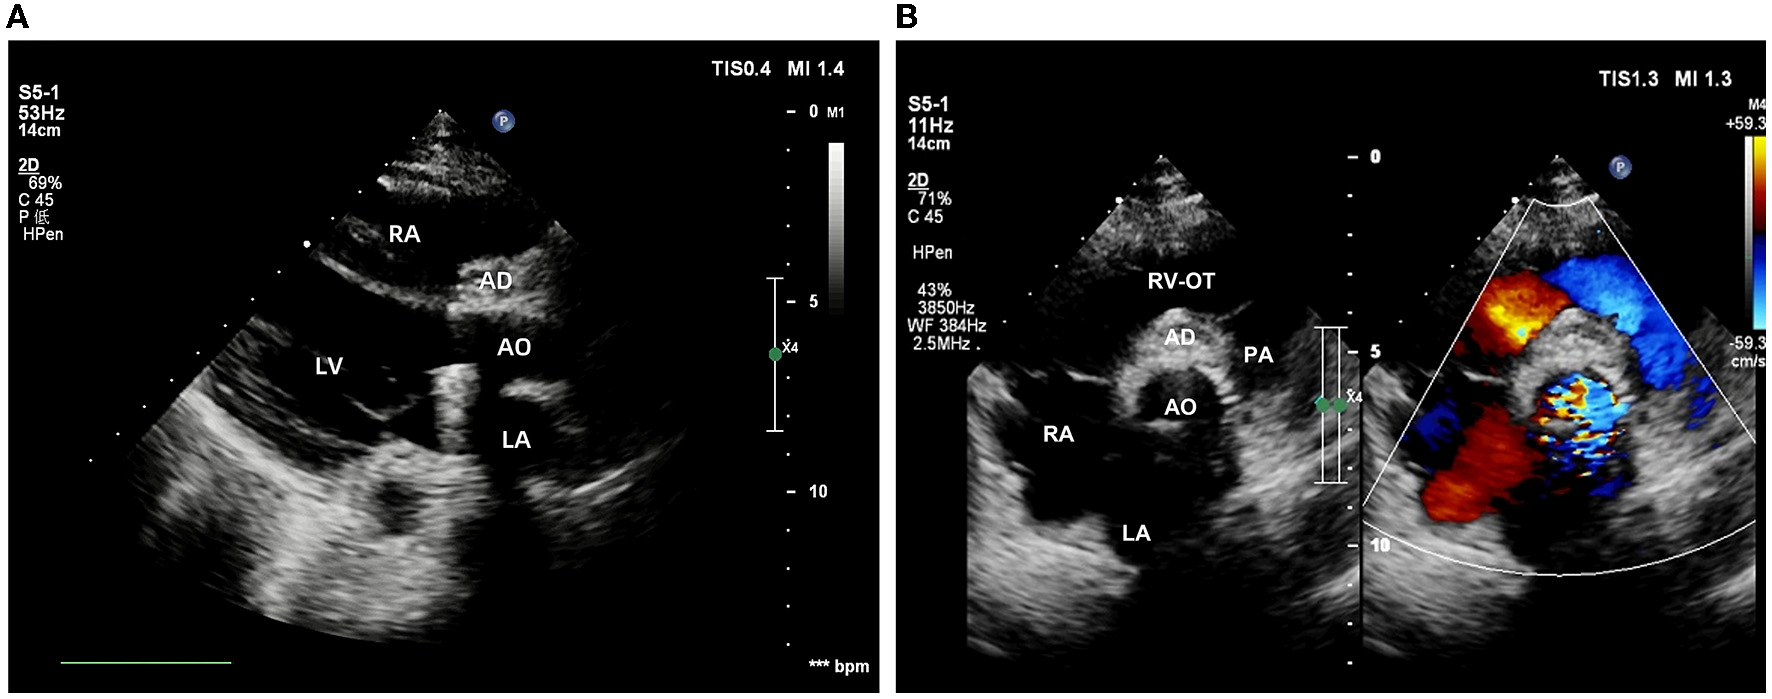

The intraoperative and post-operative blood cultures were both negative. Therefore, we performed a post-operative high-throughput sequencing examination, which showed oral streptococcal infection. The patient then received cardiotonic therapy, anti-inflammatory treatment, and other necessary symptomatic support. Post-operative echocardiography showed that the artificial aortic conduit and valves were in normal position and functioned well (Figure 4A). The closure of the bulge was successful, with no blood flow signal inside (Figure 4B). No stenosis or obstruction was observed in the opening of the coronary arteries. Post-operative blood routine examination showed that the leukocyte returned to normal at 9.21 × 109/L. The patient described that the chest pain disappeared and was discharged 15 days after the surgery. Four weeks after surgery, the follow-up echocardiography showed no positive finding.

Figure 4

Post-operative echocardiography. (A) The position and function of the artificial valved conduit are normal. (B) The aortic root bulge is successfully closed without an internal blood flow signal.